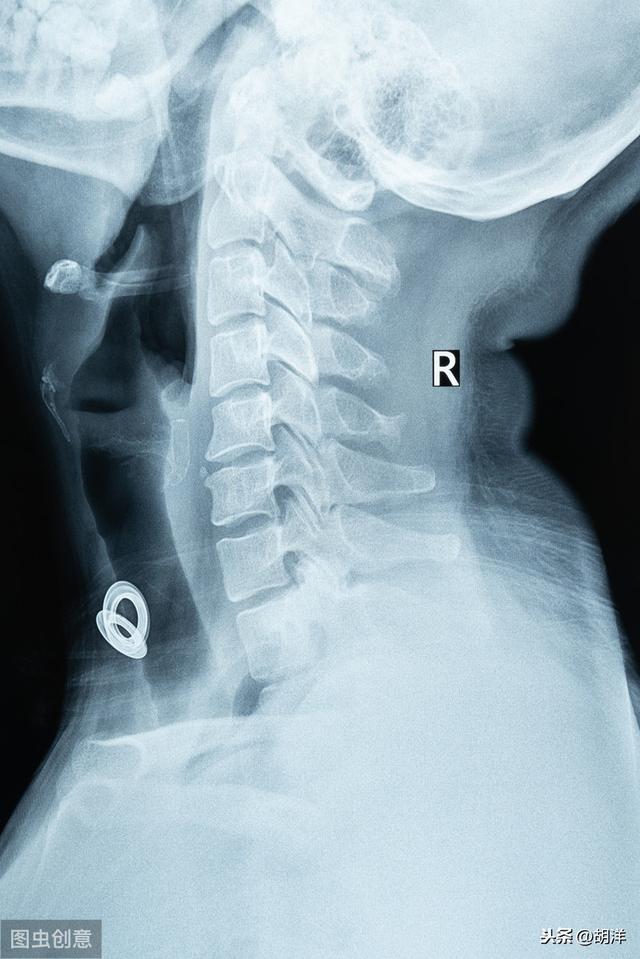

Deuxièmement, la spondylose cervicale est également une cause fréquente d'engourdissement des mains, l'insuffisance de l'apport sanguin cérébral produira également un engourdissement du membre opposé, vous pouvez donc vous rendre à l'hôpital pour confirmer le diagnostic d'un film de la colonne cervicale pour voir la colonne cervicale. Parallèlement, nous pouvons également exclure les maladies cardiovasculaires et cérébrovasculaires.

I. Spondylose cervicale

La spondylose cervicale est une maladie dégénérative du disque intervertébral cervical, une hernie discale cervicale ou des ostéophytes de la colonne cervicale, qui affecte le rétrécissement du foramen intervertébral de la colonne cervicale. Le foramen intervertébral est le canal de circulation des nerfs, les nerfs du foramen intervertébral sortent de l'innervation des nerfs de la main et du pied, pour atteindre la coordination, afin de maintenir le mouvement normal des membres du corps humain.

Si la hernie discale ou l'excroissance osseuse occupe le canal nerveux, elle comprime les nerfs, en particulier le nerf radiculaire postérieur, ce qui provoque un trouble ou une anomalie de la conduction sensorielle et un engourdissement des mains. Ce type d'engourdissement est principalement lié à la distribution des nerfs, de sorte que certains patients atteints de spondylose cervicale présentent un engourdissement des membres ou une sensation anormale, ce qui est principalement lié à la spondylose cervicale radiculaire.

1. spondylose cervicale Le type le plus courant d'engourdissement des mains est la spondylose cervicale de la racine nerveuse, principalement dans les membres supérieurs de la racine nerveuse par la saillie du disque intervertébral cervical, l'hyperplasie osseuse ou le ligament calcifié et les changements de courbure dans la pression du corps vertébral, ce qui entraîne un affaiblissement de la conduction nerveuse, qui provoque des symptômes évidents d'engourdissement des mains. En outre, lorsque la compression de la racine nerveuse est grave, il est également facile d'entraîner une faiblesse musculaire des membres supérieurs, d'un côté ou des deux côtés, voire une atrophie musculaire, ce qui affecte gravement la qualité de vie du patient. D'une manière générale, l'engourdissement des mains causé par la spondylose cervicale est le plus souvent unilatéral.

(2) Spondylose cervicale. La spondylose cervicale est la cause la plus fréquente de l'engourdissement des mains. Si les nerfs des membres supérieurs sont comprimés, il y a engourdissement et douleur dans les membres supérieurs, les bras, accompagnés des manifestations typiques de la spondylose cervicale, telles que la douleur de la colonne cervicale, la torsion défavorable, etc.

Deuxièmement, la spondylose cervicale

La spondylose cervicale peut provoquer une hyperplasie du rachis cervical, qui comprime les vaisseaux sanguins et les nerfs du cou, affectant la fonction des membres et provoquant un engourdissement des membres à différents degrés.

Troisièmement, la spondylose cervicale : la spondylose cervicale est une maladie courante chez les personnes d'âge moyen et les personnes âgées, et l'engourdissement des mains est l'un de ses symptômes. La spondylose cervicale peut être traitée par la physiothérapie, l'aiguille flottante, les pansements, les taches collapsées de la médecine chinoise et les médicaments qui activent la circulation sanguine. En général, vous pouvez faire des exercices de santé du cou en pratiquant une activité lente, et veiller à ce que la hauteur de l'oreiller soit appropriée, généralement de 7 à 9 cm, ni trop haut ni trop bas, ni trop mou ni trop dur, et que la posture pendant le sommeil soit correcte.